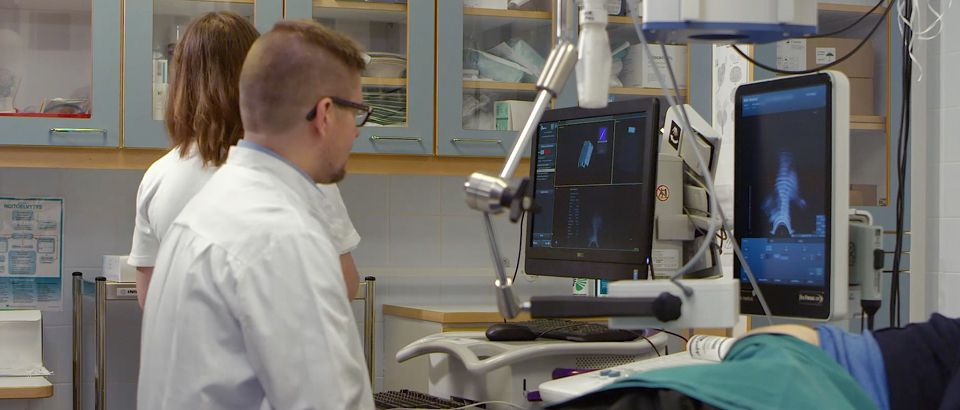

Monitor

El monitor tiene un diseño ergonómico totalmente articulado. Sus múltiples posibilidades de ajuste permiten un mayor rango de ángulos de visualización durante los procedimientos. Además, se pueden realizar ajustes de altura para obtener una mayor flexibilidad.